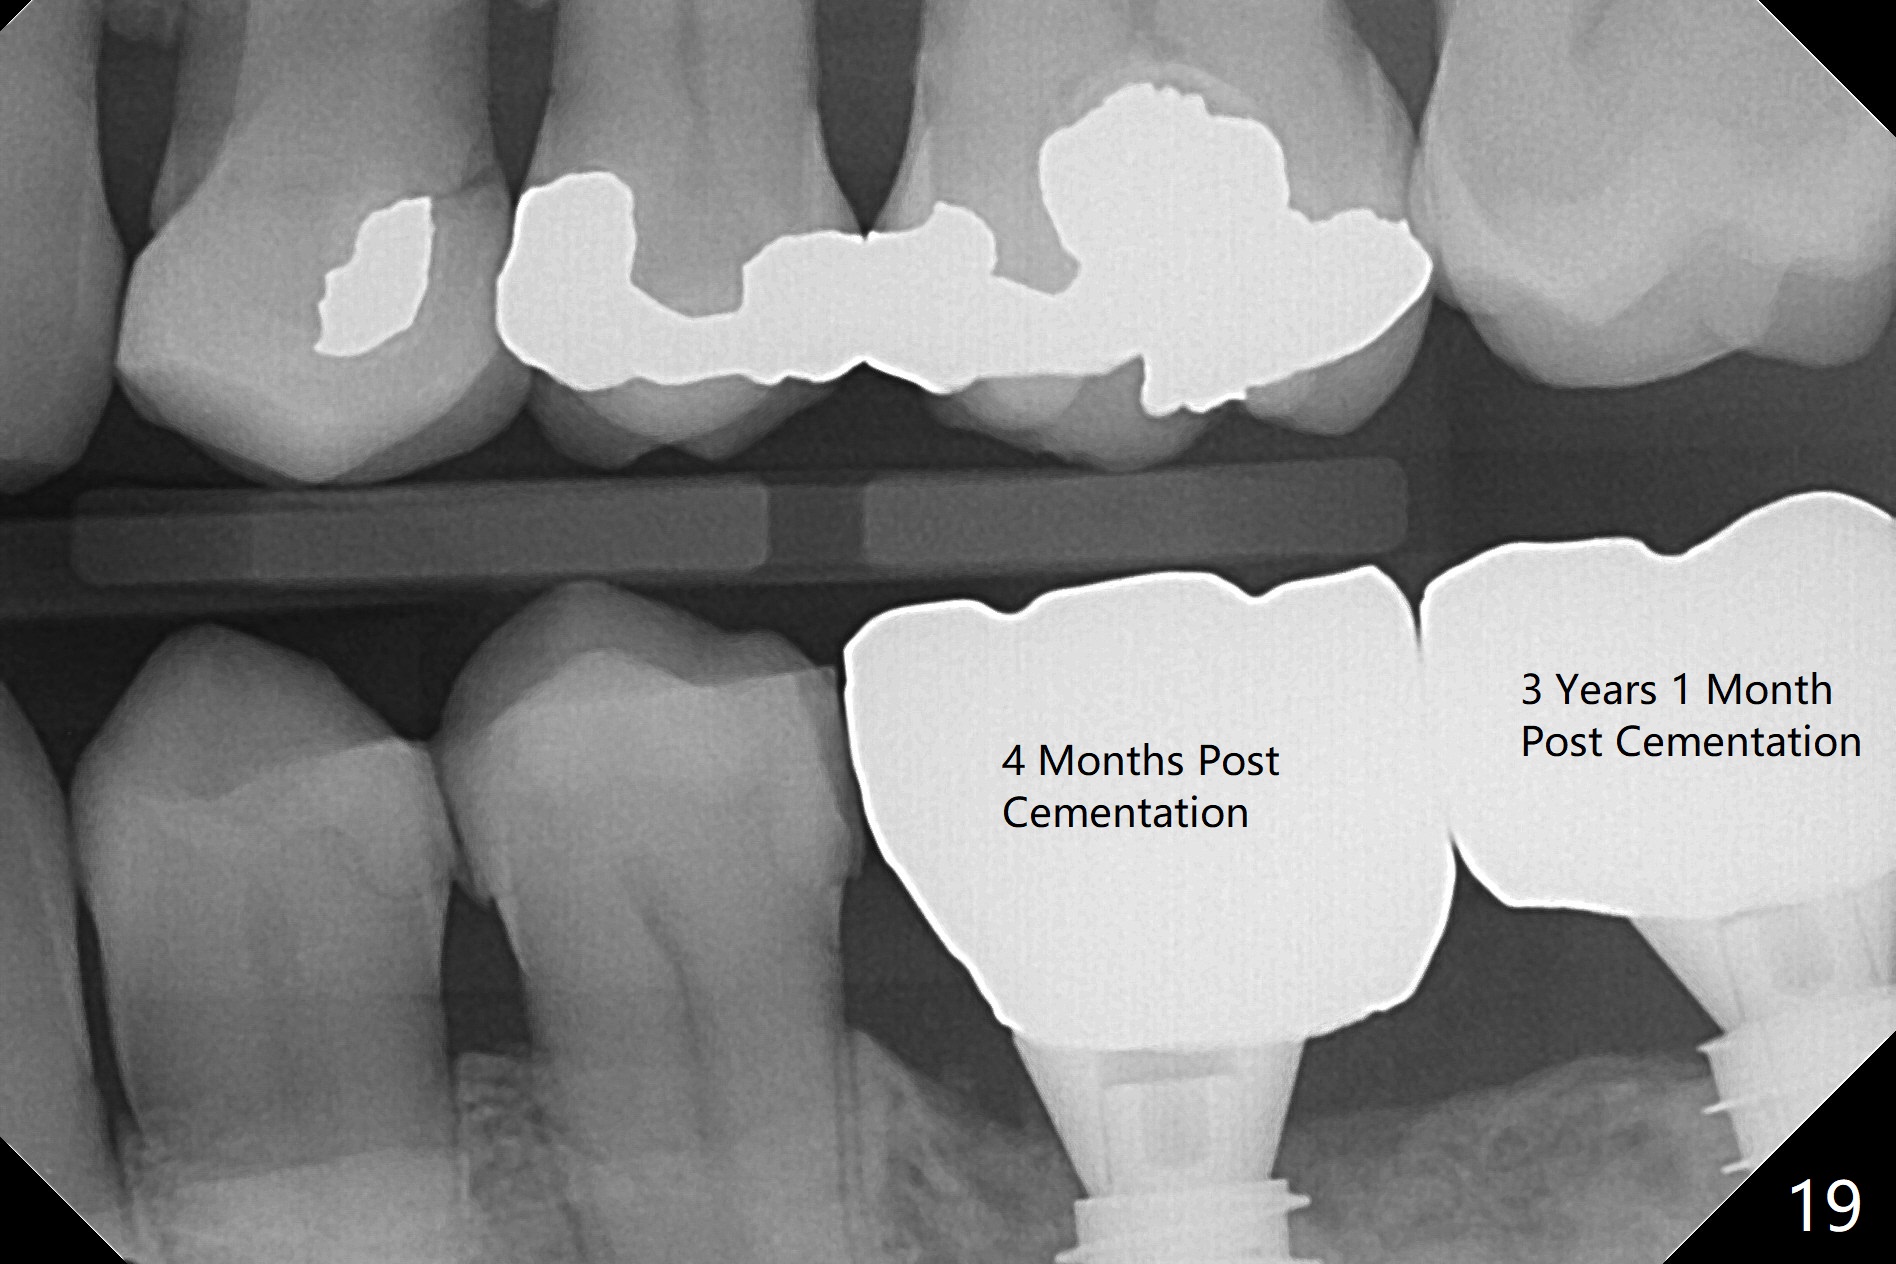

Venopuncture is conducted (Fig.1) for PRF and sticky bone (cortical chip and .5 cc ß-TCP). After use of proximators at #19, cowhorn forceps are applied, resulting in metal crown dislodgement. Since there is distal bone loss, distal socket sheath is contemplated. The tooth is sectioned. When an elevator is inserted between the roots, the distal root is loosened first. The 2 roots are removed, revealing a rounded end septum (Fig.2 S) and a larger distal socket. To avoid osteotomy deviation over the septum, a 12 mm bone trimmer is used, followed by point drill (Fig.3 *). But the lower half of the implant is deviated mesial (Fig.4) with decreased torque (~ 10 Ncm). To overcome this misfortune, the roots should not be removed until osteotomy is finished. Dual zones of bone graft is conducted. Sticky bone is placed until the plateau of the implant with a healing screw in place (Fig.4 * (bone zone)). After placement of a pair abutment, the same bone graft is packed until the margin of the abutment (Fig.5 * (soft tissue zone)). An immediate provisional is fabricated to close the socket with a piece of PRF as well. Fig.6-11 explains why the lower half of the implant deviates to the mesial socket, while Fig.12-16 illustrates how to prevent the deviation. After extraction of #19 (Fig.6,7), the crest of the septum is flattened (Fig.8 arrowhead) to prevent the initial deviation (Fig.9 red line). When a drill reaches a space (a socket, mesial in this case), the drill is deflected to the least resistant area (Fig.10 a bent red line), leading to the implant deviation apically (Fig.11 green). To prevent the apical deviation, therefore, the roots of the affected tooth is temporarily not removed (Fig.12). The osteotomy should not deviates with surgical guide because of similar density between the tooth and the bone (Fig.13). When the osteotomy is finished (Fig.14), the roots are extracted (Fig.15). The implant to be placed should not have deviation (Fig.16 green). The papillae are maintained by the immediate provisional 11 days postop (Fig.17). The incompletely seated abutment at #18 (Fig.5 <) is reseated completely 6 months postop (Fig.18). Crestal bone forms distal to #19 implant. There is no bone loss 4 months and 3 years 1 month post cementation at #19 and 18, respectively (Fig.19,20).